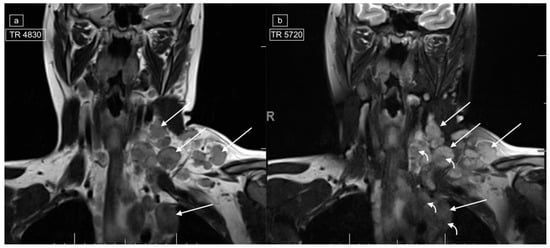

Figure 1.

Magnetic resonance imaging (MRI) in a 20-year-old female with a histologic diagnosis of nodular sclerosing Hodgkin lymphoma. Axial T2-weighted (T2w) images of the lower cervical region (a) and upper mediastinum (b) demonstrate large left cervical and left paratracheal lymphadenopathy (white arrows) exhibiting low T2 signal. On corresponding post-gadolinium T1 imaging of the lower cervical region (c) and upper mediastinum (d), the abnormal lymph nodes show central foci of hypo-enhancement (black arrows).